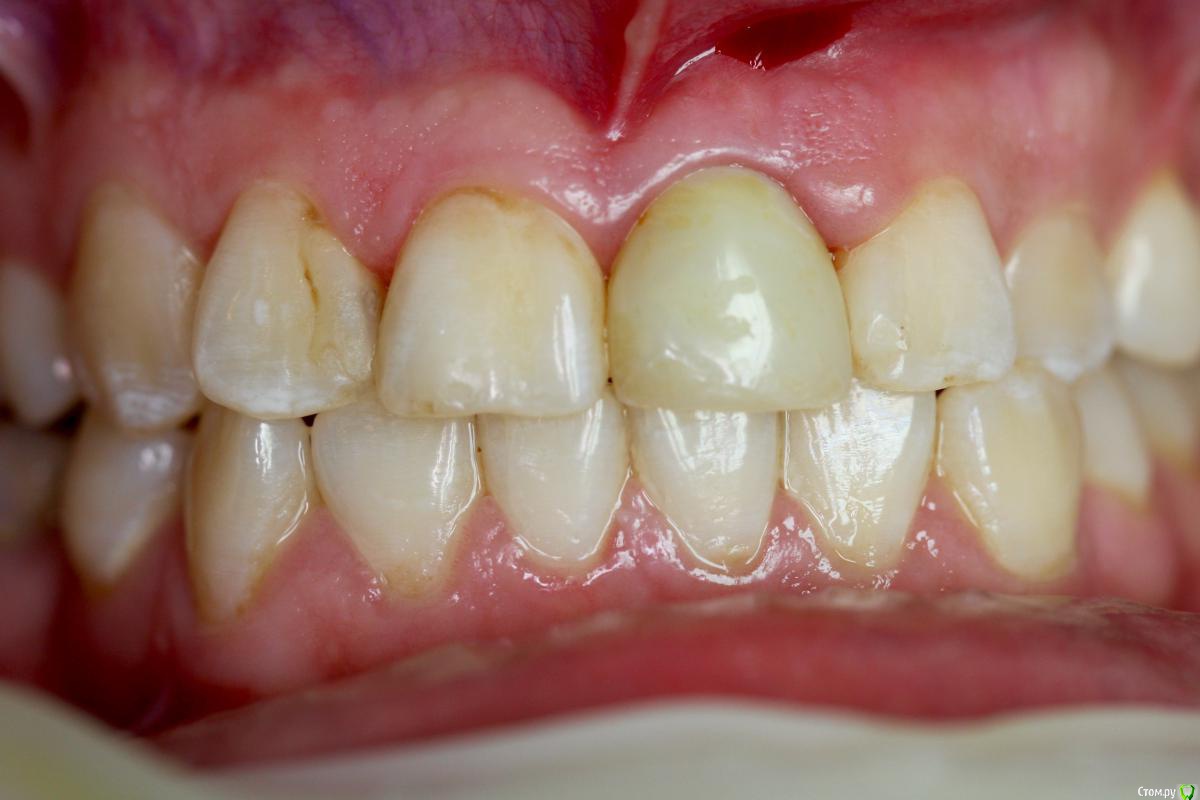

Zorrro Опубликовано 29 февраля, 2016 Автор Поделиться Опубликовано 29 февраля, 2016 (изменено) Через два дня пациент меня неприятно удивил.И ,безусловно,правильно было бы отменить операцию и ограничиться удалением,но… Вот такой был сюрприз под носом с нечищенными зубами.Обговорив риски,перекрестившись начали.Во время операции фото не делал.Слизистая в проекции 21 была сильно истончена острым гнойным процессом,буквально светилась.в итоге после эвакуации гноя промыл фурацилином,установил анкилос А11,подсыпал остеопласт вестибулярно и укрыл это всё сст из бугра в качестве мембраны.ещё один сст пошёл навременный абатмент в виде "шашлыка".Через 10 дней Через 4 месяцас рекомендацией замены пломбы на 12 у своего доктора мы ипопрощались.пациентка осталась глубоко удовлетворённой,а это главное. Изменено 29 февраля, 2016 пользователем Zorrro 4 Ссылка на комментарий